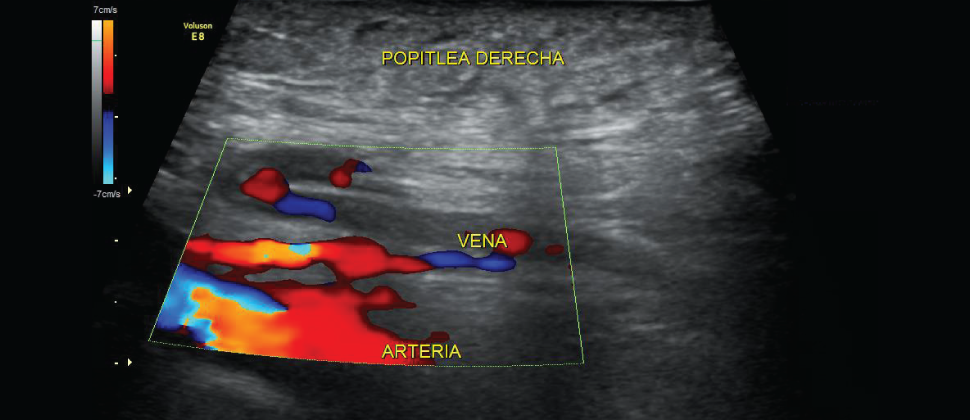

Se pueden analizar las arterias del útero de la madre (arterias uterinas). Esto es muy importante en el caso que la madre presente hipertensión en el embarazo o en el caso de que haya un retraso del crecimiento intrauterino del bebé para poder determinar las causas y actuar según las mismas.